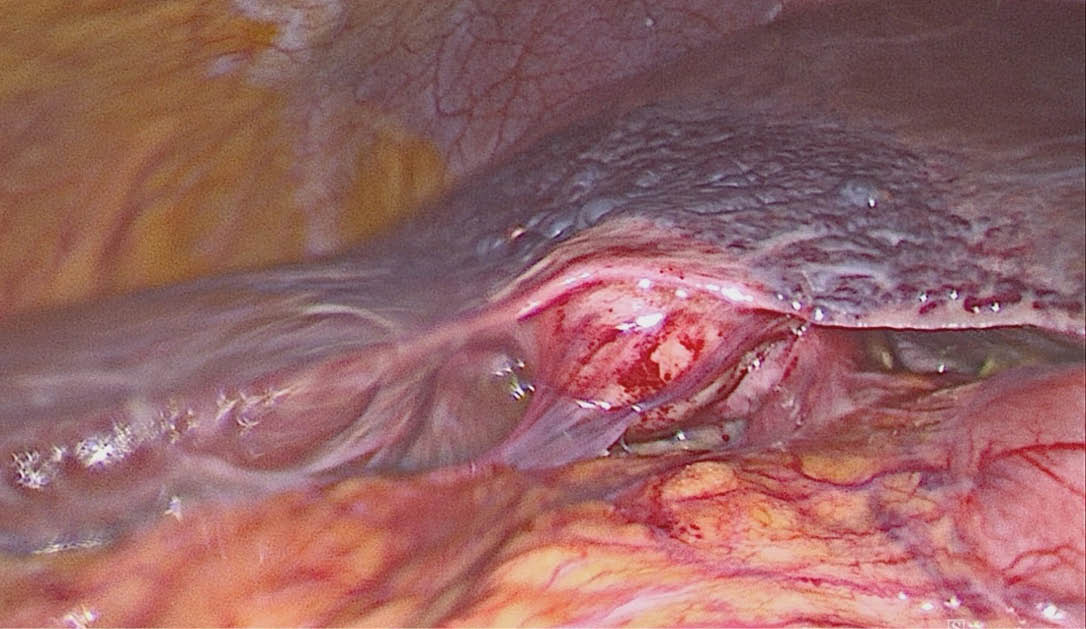

Unter diaphanoskopischer Kontrolle (Abb. 5) mussten die 2 weiteren epigastrischen Arbeitstrokare etwas mehr rechtsseitig positioniert werden. Intraoperativ (Abb. 6) stellte sich die Gallenblase sowohl akut als auch chronisch entzündlich verändert dar. Die Leber zeigte makroskopisch venöse Malformationen sowie einen beginnend kleinknotigen Parenchymumbau. Die laparoskopische Cholezystektomie verlief ohne Komplikationen, auf die Einlage von lokalem Drainagematerial konnte verzichtet werden. Die pathohistologische Aufarbeitung (Abb. 7) zeigte eine chronisch-fibrosierende Cholezystitis mit Gallenblasenwandverdickung ohne Anhalt für Malignität.

Abb. 5: Intraoperativer laparoskopischer Befund des Hämangioendothelioms der Rumpfwand linksseitig sowie auf dem Ligamentum triangulare sinistrum. Nebenbefundlich kleiner von-Meyenburg-Komplex im Lebersegment-II/III-Übergang bei Leberzirrhose

Abb. 6: Intraoperativer laparoskopischer Befund einer teils chronischen, teils akuten Cholezystitis sowie einer venösen Malformation der Leber (hepatisches Hämangiom) mit kleinknotigem Parenchymumbau i. S. einer Leberzirrhose